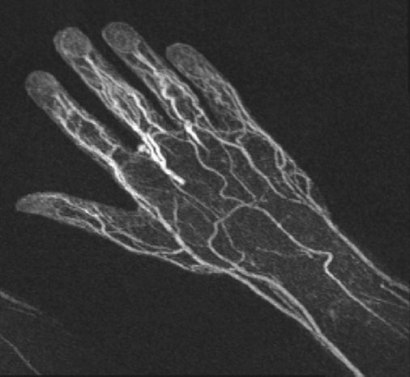

В сентябре 2019 г наш МРТ томограф был укомплектован еще одной современной радиочастотной катушкой, что позволило СДЦ не только значительно улучшить визуализацию изображений при МРТ исследованиях, но и проводить уникальные для Самары и России медицинские исследования МРТ ангиографию лёгочных артерий, артерий верхних и нижних конечностей.

Самарский диагностический центр предлагает альтернативу в этой безвыходной ситуации для специалиста и пациента — МРТ ангиографию сосудов. При этом полностью исключается воздействие вредного ионизирующего излучения и побочных реакций от введения рентгеноконтрастного препарата на организм человека.

Благодаря инновационной технологии, внедренной в СДЦ–кардиологи и сосудистые хирурги получат результаты исследований своих пациентов (ангиография лёгочных артерий, артерий верхних и нижних конечностей) даже при непереносимости пациентами контрастных препаратов на основе йода.